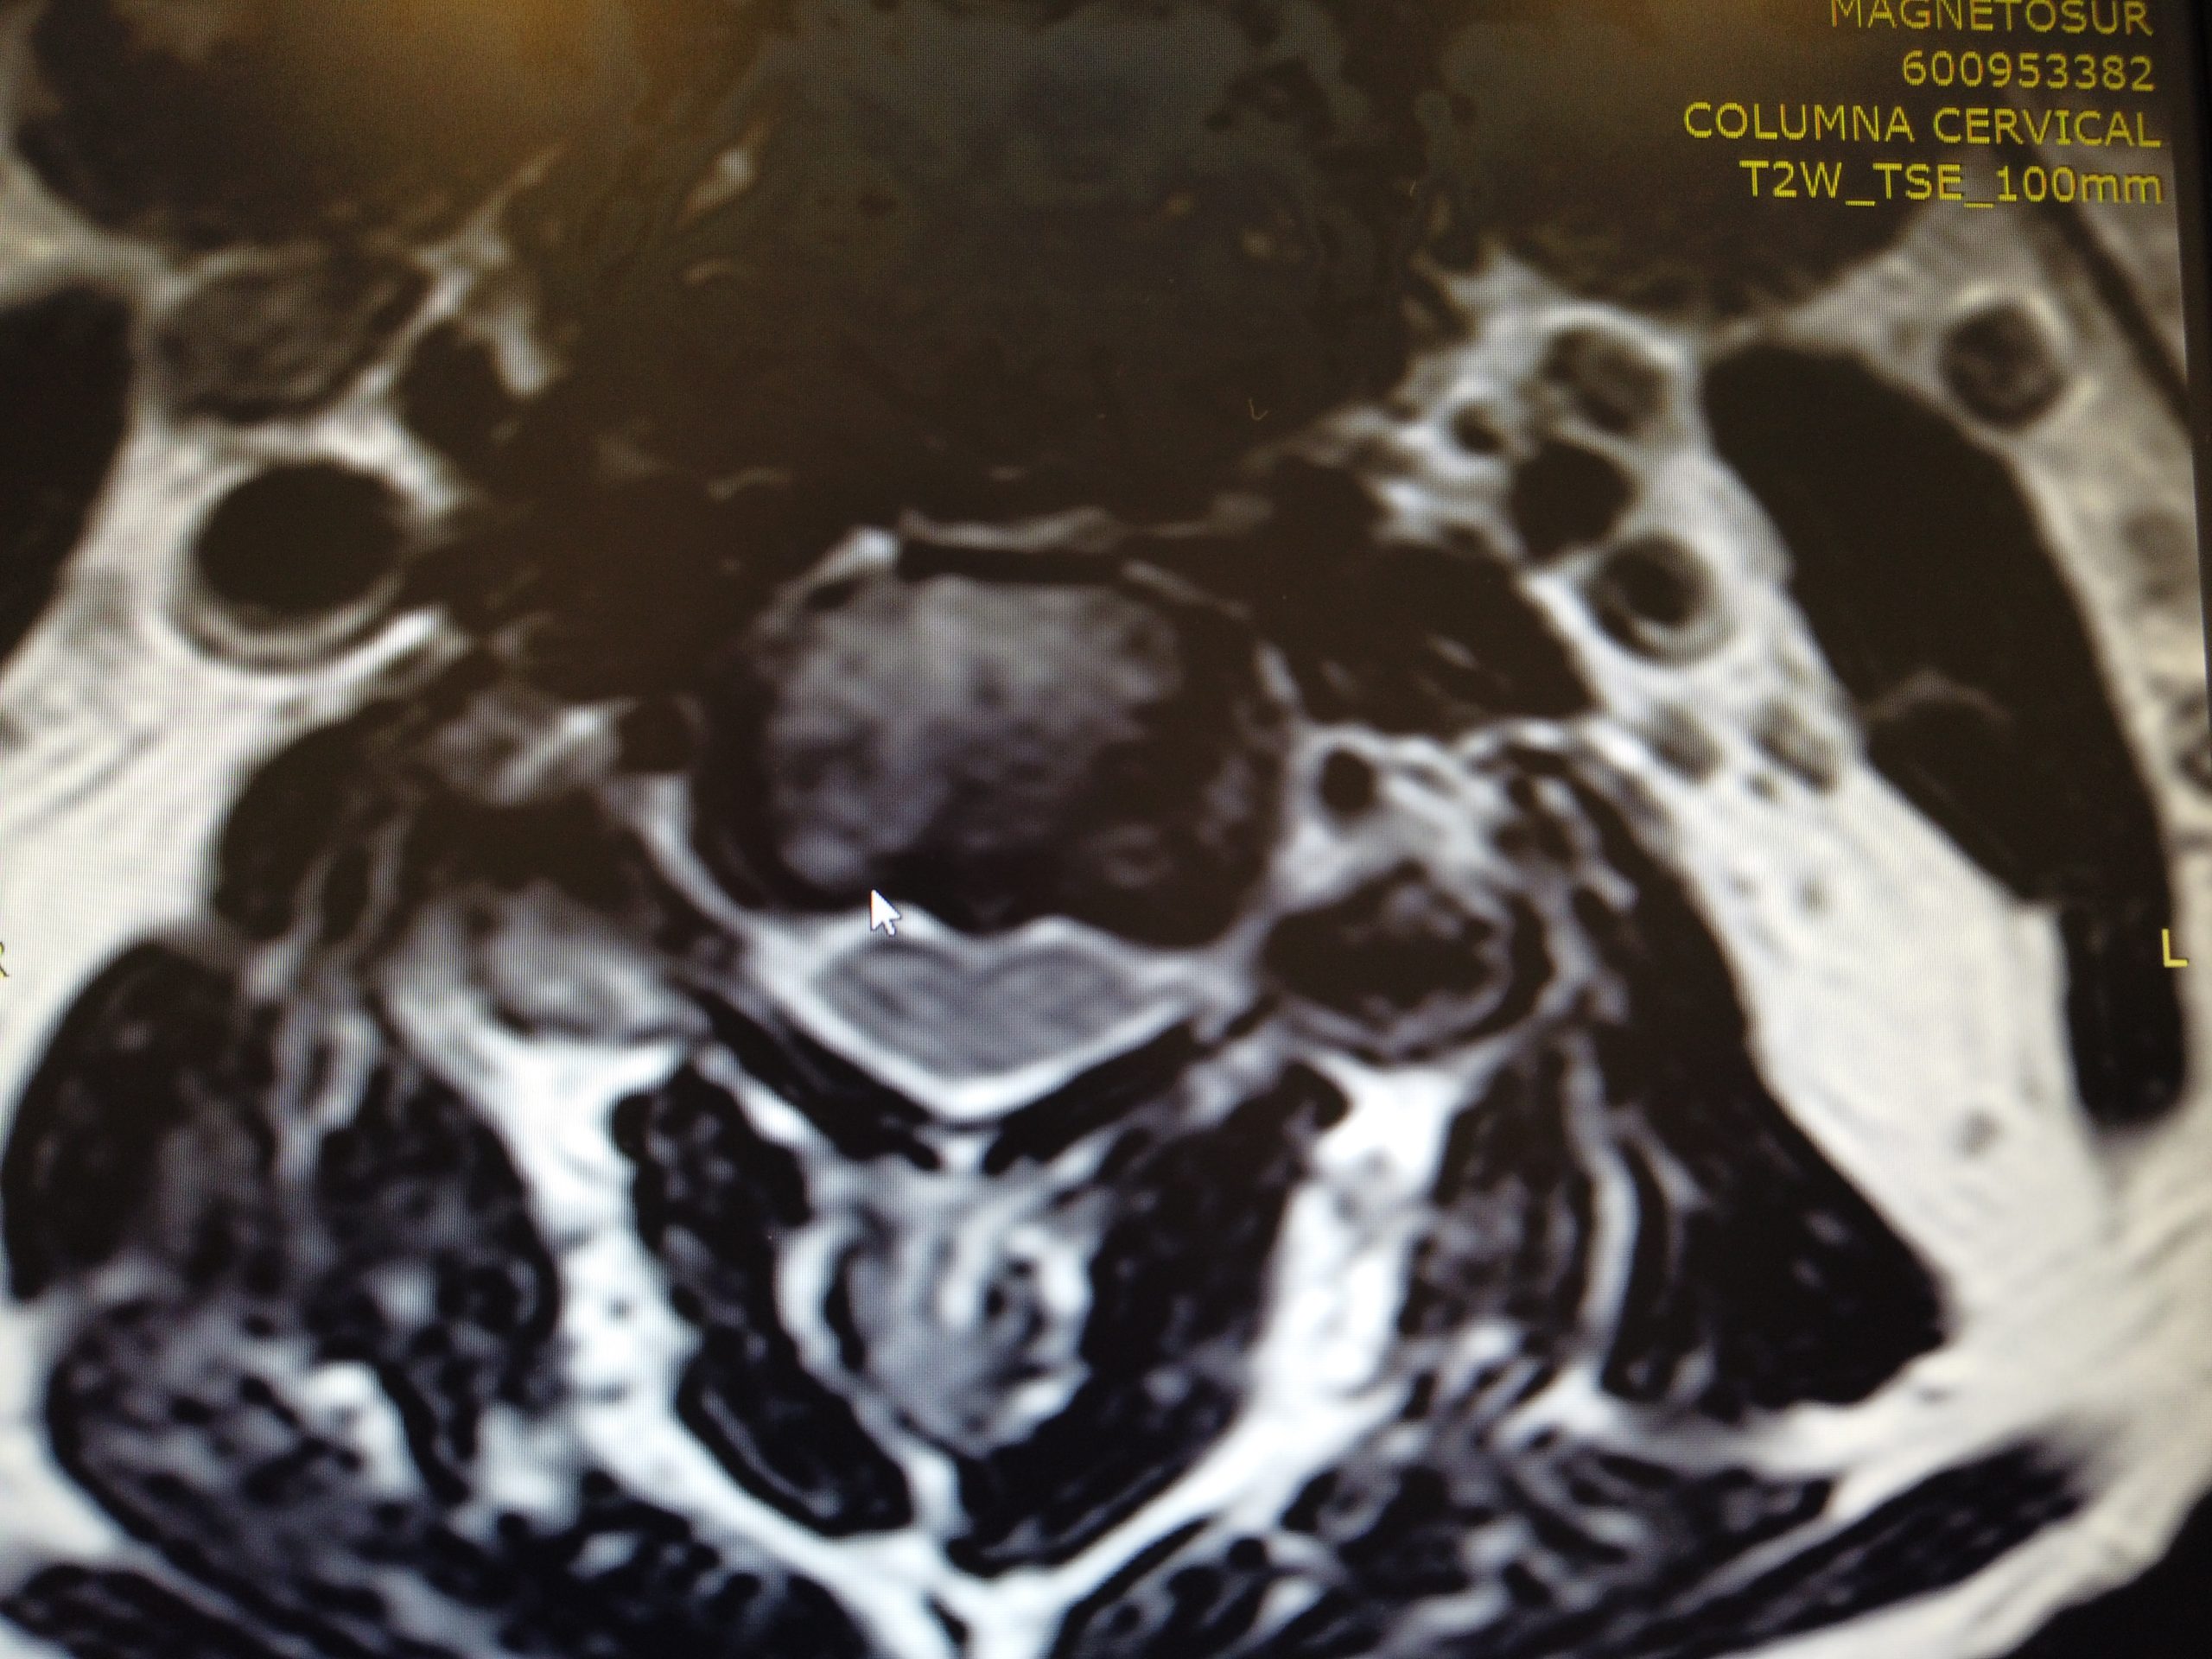

Caso de extrema dificultad en el que podemos ver a un paciente con dolor crónico cervical, parentesias MMSS y hormigueo en los miembros superiores.

Nos encontramos ante un paciente con dolor agudo que presenta tres hernias discales cervicales. Su situación no mejoraba con medicación ni tratamiento.